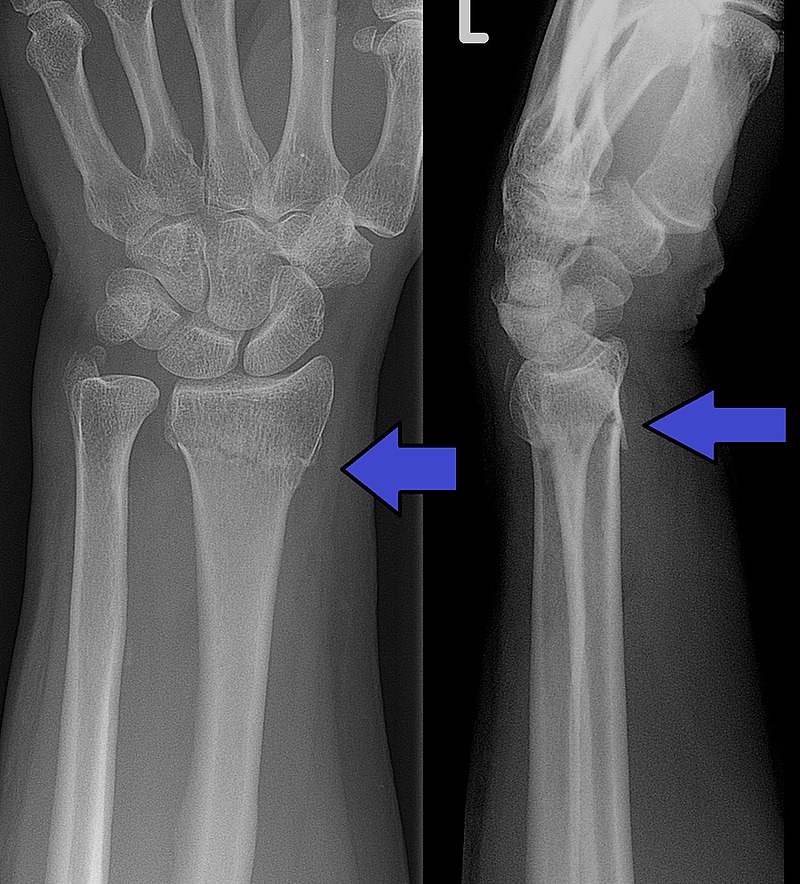

Hulpafdelingen van ziekenhuizen in de regio houden rekening met een flinke toename van het aantal patiënten dat binnenkomt met botbreuken door sneeuw en ijs.

De spoedeisende hulpposten zien nu nog geen stijging van beenbreuken of polsfracturen maar verwachten wel een flinke toename aankomend weekeinde, door verwachte ijspret en aanhoudende gladheid de komende dagen. Premier Rutte riep vorige week nog op voorzichtig te zijn op het ijs. Schaatsverwondingen zouden nog meer druk op de zorg kunnen leggen, die nog altijd overbelast is door de zorg voor coronapatiënten.

De tachtig Nederlandse spoedeisendehulpafdelingen signaleerden vorige week maandag toen het plotseling glad was wel extreme drukte. Artsen behandelden tot twee keer meer patiënten dan normaal. Zij waren bijna allemaal slachtoffer van de gladheid. Afdelingen hebben extra personeel stand-by staan, voor het geval dat de EHBO posten toch vollopen.